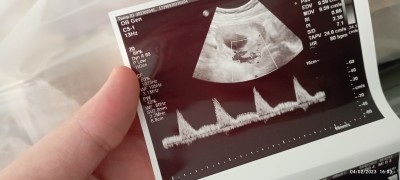

Hanımlar merhabalar bugün doktora gittim ve şimdi resimde de paylaştigim gibi alltagi net cizgilerine benzeyen çizgiler bende kan pıhtılaşmasi olduğunu ve doğuma kadar kan iğnesi ve coraspirin kullanmam gerektiği söylendi başından bu tür durum geçen veya farklı bir doktara baş vuran arkadaşlar varsa yardımcı olabilir misiniz

Gebelik haftası 12+1